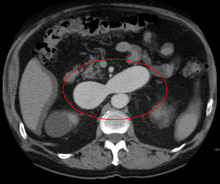

An arterial venous malformation of the left kidney and a simple cyst of the right kidney